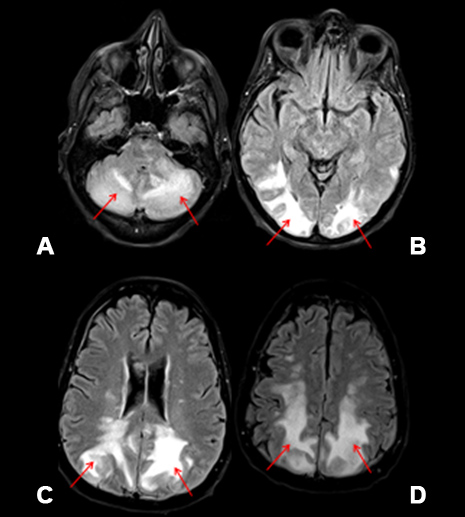

Figure 2: Corresponding axial fluid attenuated inversion recovery (FLAIR) MRI images obtained through the level of the cerebellum (A), occipital cortex (B), parietal cortex (C), and frontal cortex (D). The vasogenic edema is much better and more easily visualized than on CT. The vasogenic edema (red arrows) seen as increased signal (white) on the MRI images.

This is a 67-year-old female patient with DLBCL with extensive neoplastic involvement of the lower thorax, abdomen, pelvis, and bilateral hydronephrosis with diffuse tumor infiltration of the left renal hilum. She was started on aggressive chemotherapy with DAEPOCH- R. She was also being treated with intrathecal chemotherapy with methotrexate (MTX). She was recently discharged from the hospital three days ago after completion of her first cycle of chemotherapy. She presented to the emergency room with generalized weakness, confusion and fevers. She had a maximum temperature of 103.1 °F. She denied any nausea, vomiting, diarrhea, chest pain, or shortness of breath. She started complaining of loss of vision in the emergency room. A quick ophthalmic examination showed that her pupils were round, regular, and reactive to light with no gross deficits. Suddenly, she suffered a grand mal seizure and was unresponsive following the seizure. She was immediately intubated for airway protection. She was noted to have severe hypertension and was started on propofol. Computed tomography (CT) of the head demonstrated bilateral, symmetrical vasogenic edema in the right and left posterior frontoparietal and occipital cortex and cerebellar hemispheres (Figure 1). Magnetic resonance imaging (MRI) of the brain showed vasogenic edema in the cerebellum and parieto-occiptal lobes with no restricted diffusion consistent with PRES (Figure 2). Electroencephalogram (EEG) performed under propofol sedation, showed diffuse delta 2–3.5 Hz waves with theta activity of 4–5 HZ with a poor degree of reactivity. There was no ictal evolution or epileptiform discharges (Figure 3). Photic stimulation produced no additional response. She was started on levetiracetam 1500 mg BID and lacosamide 100 mg BID. She was monitored with routine EEGs that had occasional generalized periodic discharge (GPD). It was felt the PRES was secondary to DA-EPOCH-R with hypertension. She was monitored in the hospital for 13 days and post-discharge had significant clinical improvement. She is ambulating and performing most of her activities of daily living with some assistance from her family. She does report poor short-term memory. She remains on levetiracetam 1500 mg BID and lacosamide 100 mg BID with no seizure or seizure like activity. Her family reports her blood pressures have been under relatively good control.